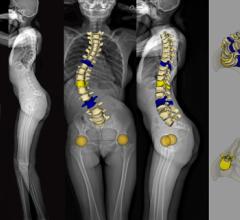

EOS imaging, a in 2D/3D orthopedic medical imaging, announced today that the U.S. Food and Drug Administration (FDA) has approved spineEOS, an online 3D planning software for spine surgery based on EOS stereo-radiographic 2D/3D imaging.